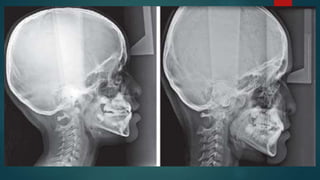

Superimposition o f the radiographs on the anterior cranial base

structures during wear o f a chin cap shows a dramatic change in

mandibular position.

This change occurred through correction of the functional forward

positioning o f the mandible. After the change o f the position,

forward growth o f the chin was more inhibited, and the chin was

displaced downward. Superimposition after discontinuation o f the

chin cap shows almost no skeletal change. The changes accomplished

during chin cap wear seemed to be retained well.